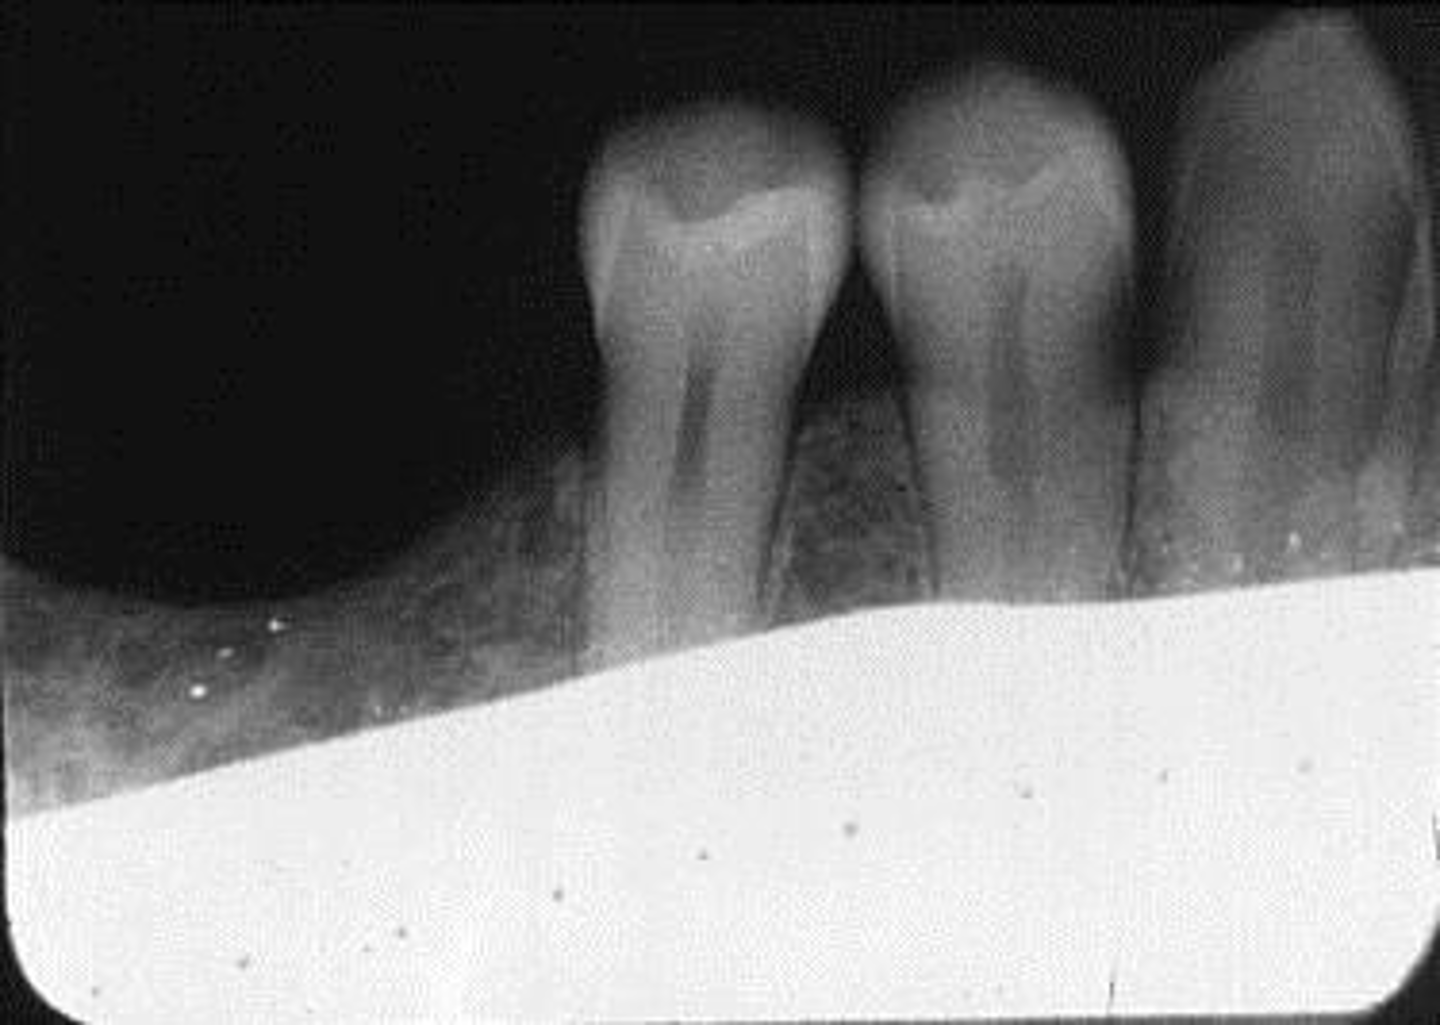

Damage, elongation, can't see apices

What is this error?